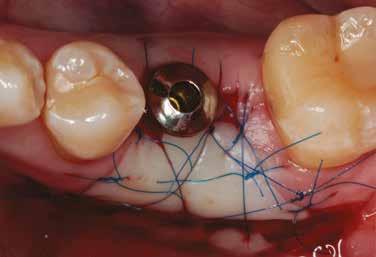

A behelyeztt implantátum primer stabilitását megfelelőnek ítéltük (kb. 40 Ncm) az azonnali terheléshez (9. kép).

Az extrakciót megelőző szituációs lenyomat alapján gyári, titán, ideiglenes abutment felhasználásával, a szék mellett készített, csavaros rögzítésű, azonnali akrilát ideiglenes koronával láttuk el, melyet 20 Ncm nyomatékkal rögzítettünk (10. kép). Az azonnali terhelés szabályainak megfelelően, az ideiglenes korona nem volt kontaktusban a szomszédos és az antagonista fogakkal.

6. kép: Implantátum-ágy preparáció. 7. a–b. képek: Implantátum behelyezés. 8. kép: A behelyezett implantátum. 10. a–b képek: Azonnali ideiglenes korona készítése. 9. kép: Megfelelő primer stabilitás.